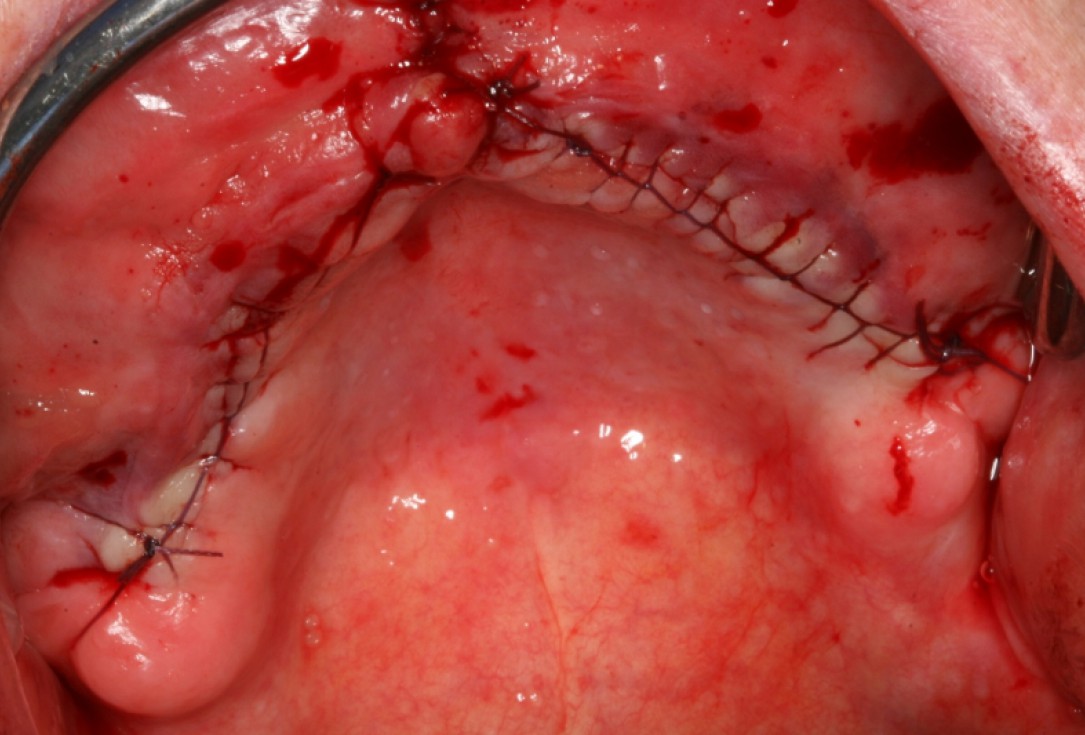

06/10 - Tight wound closure with a continuous seam following the periost splittingCircular bone splitting with maxresorb® & collprotect® membrane - PD Dr. J. Neugebauer